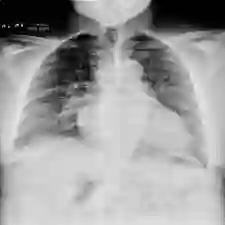

Recent advances in image-text pretraining have significantly enhanced visual understanding by aligning visual and textual representations. Contrastive Language-Image Pretraining (CLIP) has played a pivotal role in multimodal learning. However, its focus on single-label, single-granularity alignment limits its effectiveness in complex domains such as medical imaging, where images often correspond to multiple high-level labels (e.g., disease categories) across different annotation granularities (e.g., diagnostic description, clinical explanation). To address this, we propose Multi-Granular Language Learning (MGLL), a contrastive learning framework designed to improve both multi-label and cross-granularity alignment. MGLL leverages structured multi-label supervision, integrates textual descriptions across granularities, and introduces soft-label supervision with point-wise constraints to enhance alignment. MGLL employs smooth Kullback-Leibler (KL) divergence to ensure cross-granularity consistency while maintaining computational efficiency as a plug-and-play module for vision-language models. Pretrained on our constructed large-scale multi-granular datasets and evaluated across multiple datasets, MGLL outperforms other state-of-the-art methods in downstream tasks. The code is available at https://github.com/HUANGLIZI/MGLL.